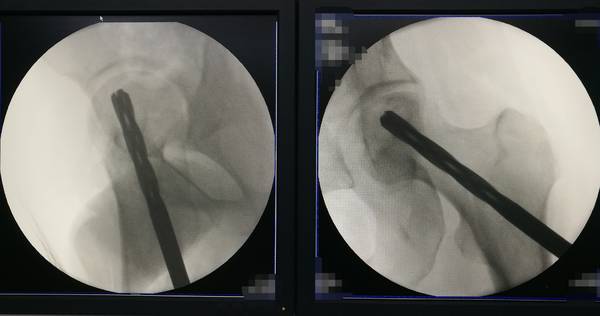

股骨头坏死

死骨刮除扩髓

IMG_20190115_200244.jpg

IMG_20190115_200120.jpg

IMG_20190115_195953.jpg

IMG_20190115_195929.jpg